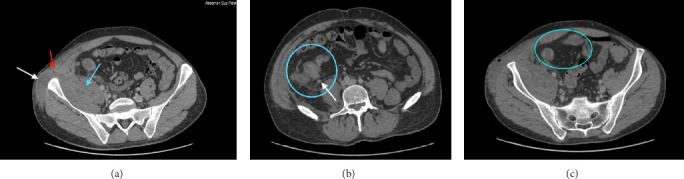

Iliopsoas abscess (IPA) is a rare but potentially life-threatening complication that may occur in patients with Crohn's disease. We present the case of a 28-year-old male with Crohn's disease who developed a complicated IPA. Diagnosis was confirmed via CT imaging and colonoscopy, revealing a fistulous connection to the terminal ileum. The treatment involved percutaneous drainage (PCD), antibiotics, and infliximab. Timely diagnosis, appropriate imaging, and multidisciplinary care are critical to prevent morbidity and recurrence in patients with Crohn's disease complicated by IPA. This case highlights the importance of personalized treatment strategies and close follow-up in managing Crohn's-related IPA.